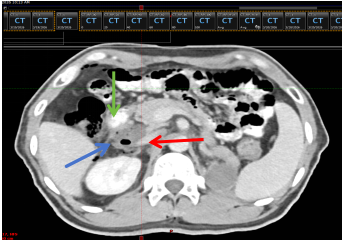

图3 未植入隔离胶定位CT(红色箭头为下腔静脉靶区,蓝色箭头为十二指肠)

图6 隔离胶植入后定位CT

(红色箭头为下腔静脉,绿色箭头为十二指肠,蓝色箭头为隔离胶)